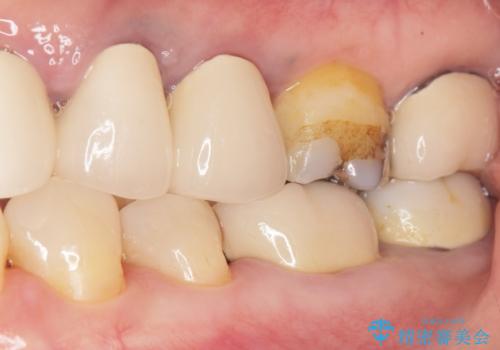

- 詰め物の境目が黒いことを気にされ、来院された患者様です。

精査したところ、左下の奥歯(左下5)のプラスチックの詰め物と歯の境目が虫歯になり、黒くなっていました。

古い詰め物とう蝕を除去し、審美的で適合が良く二次う蝕になりにくいセラミックインレーによる修復を行いました。